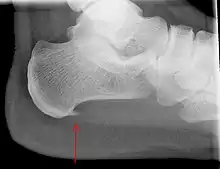

Heel bone with heel spur (red arrow)

An incidental finding associated with this condition is a heel spur, a small bony calcification on the calcaneus (heel bone), which can be found in up to 50% of those with plantar fasciitis.[6] In such cases, it is the underlying plantar fasciitis that produces the heel pain, and not the spur itself.[13] The condition is responsible for the creation of the spur though the clinical significance of heel spurs in plantar fasciitis remains unclear.[12]

Medical imaging is not routinely needed. It is expensive and does not typically change how plantar fasciitis is managed.[16] When the diagnosis is not clinically apparent, lateral view X-rays of the ankle are the recommended imaging modality to assess for other causes of heel pain, such as stress fractures or bone spur development.[7]

The plantar fascia has three fascicles-the central fascicle being the thickest at 4 mm, the lateral fascicle at 2 mm, and the medial less than a millimeter thick.[20] In theory, plantar fasciitis becomes more likely as the plantar fascia's thickness at the calcaneal insertion increases. A thickness of more than 4.5 mm ultrasound and 4 mm on MRI are useful for diagnosis.[21] Other imaging findings, such as thickening of the plantar aponeurosis, are nonspecific and have limited usefulness in diagnosing plantar fasciitis.[13]